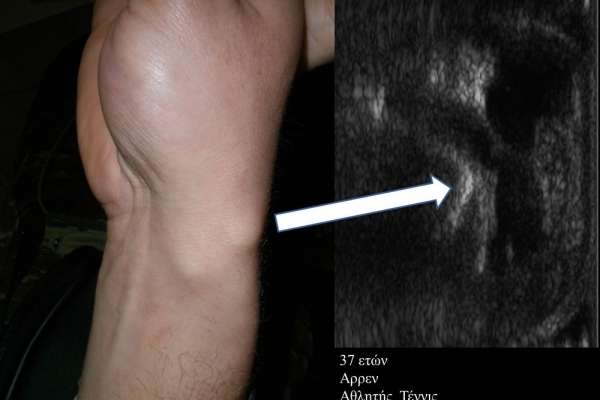

- Ακρου Ποδός/ Πέλματος (πχ απονευρωσίτιδα)